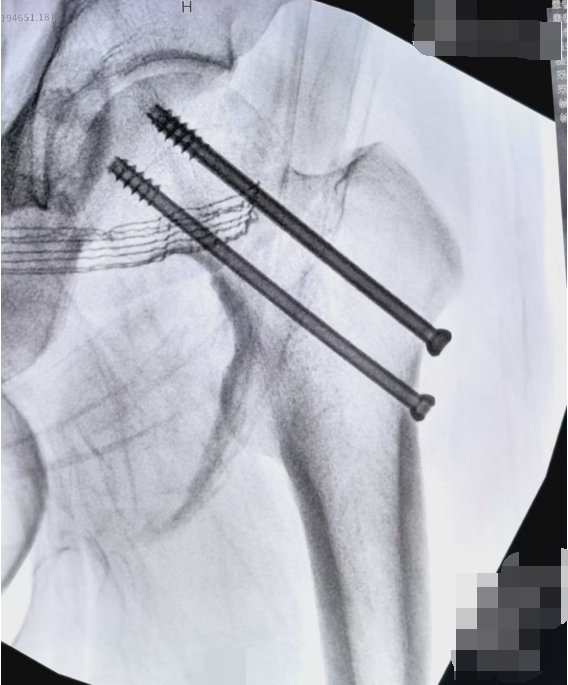

在骨科手术导航机器人的辅助下,团队精准复位骨折端,置入内固定装置,手术过程一气呵成,没有出现任何并发症。

当手术顺利完成的消息传来,王先生的家人悬着的心终于落地,紧紧握着医护人员的手连声道谢:“真的太感谢你们了,要是在浙江等到初八,我们真不知道该怎么办。”